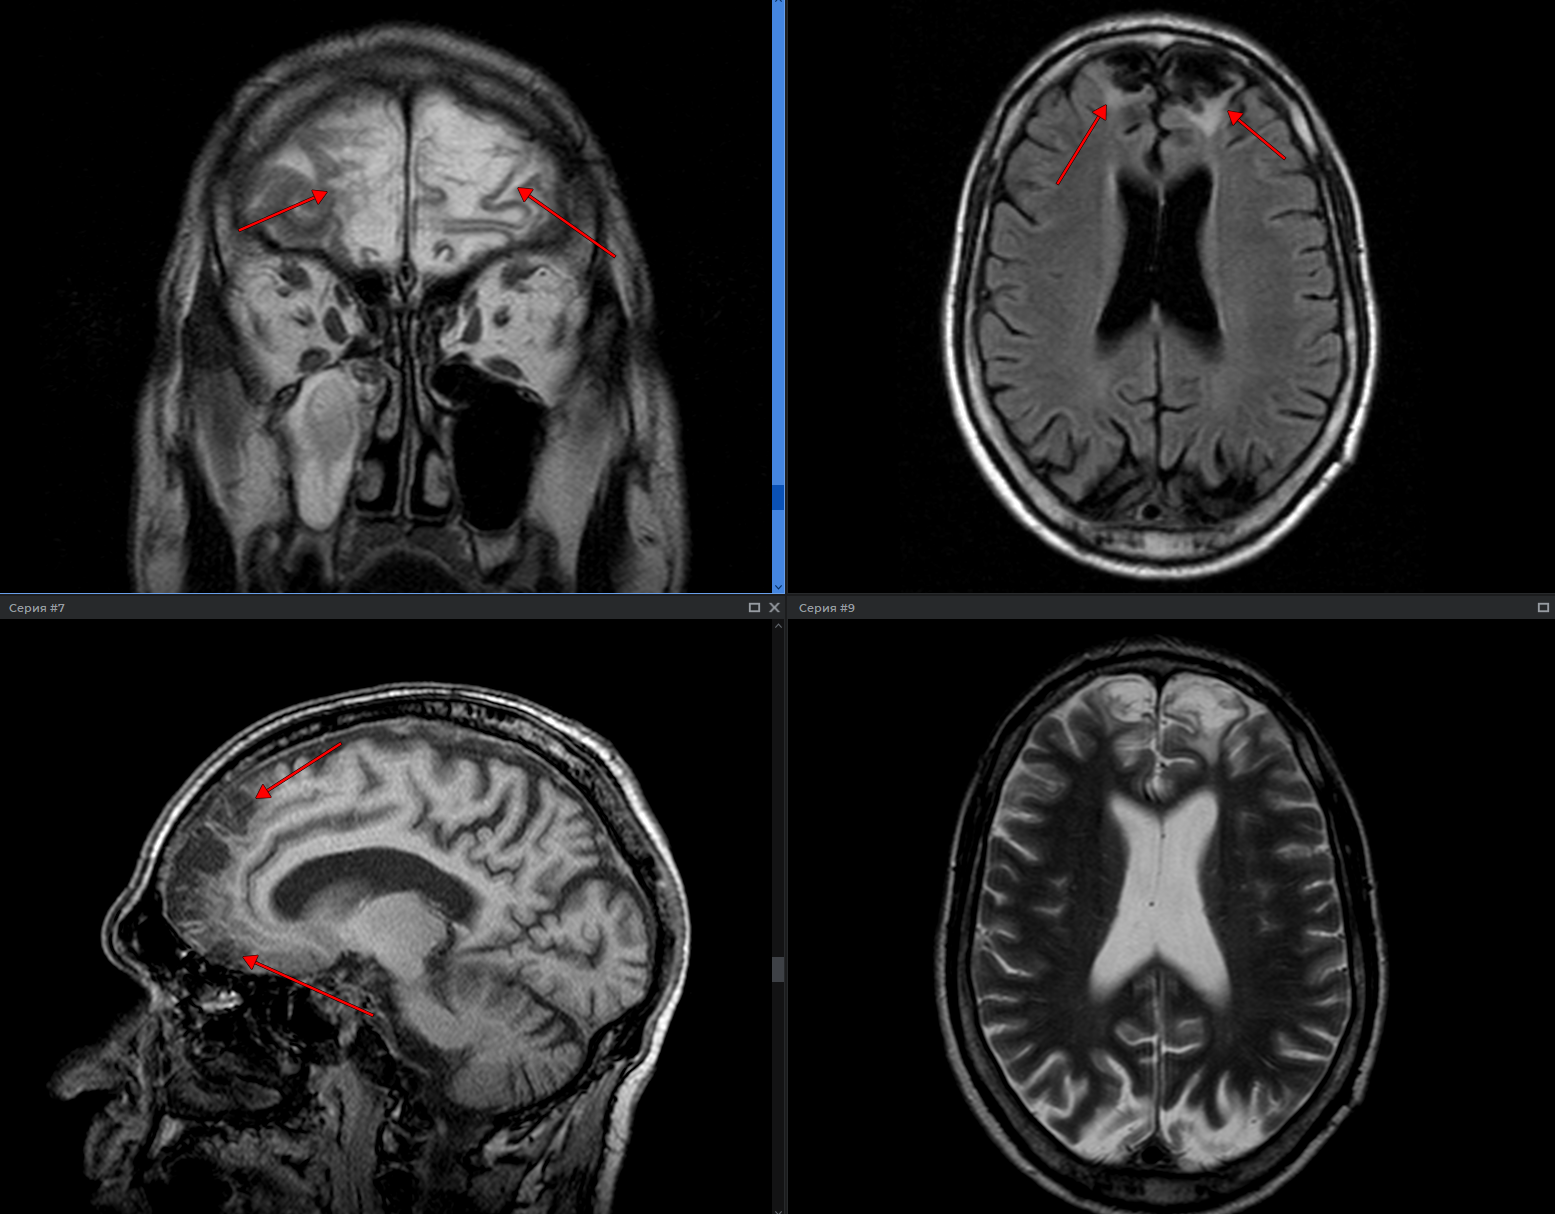

В современном мире технологии проникают во все сферы нашей жизни, и медицина не являеться исключением. Мы, как команда разработчиков, осознали огромный потенциал искусственного интеллекта (ИИ) в улучшении диагностики и лечения заболеваний. Нашей целью стало создание системы, способной анализировать изображения магнитно-резонансной томографии (МРТ) для оценки степени воспаления. Это сложная, но невероятно важная задача, ведь точная и своевременная диагностика – залог успешного лечения.

Воспалительные процессы в организме могут быть причиной множества заболеваний, от артрита до рассеянного склероза. Оценка степени воспаления играет ключевую роль в постановке диагноза и определении тактики лечения. МРТ является одним из самых эффективных методов визуализации, позволяющих получить детальные изображения внутренних органов и тканей. Однако анализ МРТ-снимков – трудоемкий и времязатратный процесс, требующий высокой квалификации от врача-радиолога. Даже опытные специалисты могут допускать ошибки из-за усталости или субъективного восприятия.

Для анализа изображений МРТ мы решили использовать сверточные нейронные сети (CNN). CNN доказали свою эффективность в задачах компьютерного зрения, таких как распознавание изображений и обнаружение объектов. Мы выбрали архитектуру U-Net, которая особенно хорошо подходит для сегментации медицинских изображений. U-Net позволяет выделять области интереса на снимках МРТ, такие как области воспаления.

После обучения мы провели тщательную оценку нашей модели на независимой тестовой выборке. Результаты показали, что наша система способна с высокой точностью определять степень воспаления на МРТ-снимках.

После успешного обучения и оценки модели мы приступили к интеграции нашей системы в существующую медицинскую инфраструктуру. Мы разработали веб-интерфейс, который позволяет врачам-радиологам загружать МРТ-снимки и получать результаты анализа. Наша система предоставляет визуализацию областей воспаления и оценку их степени.